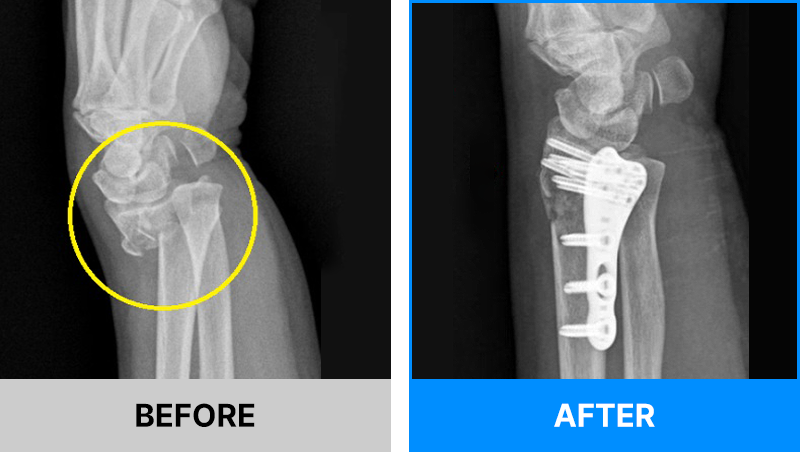

왜 당일 입퇴원 수술일까요?

오래 입원할 필요가 없기 때문입니다.

서울거탑정형외과에서는 전신마취, 척추마취가 아닌

국소부분마취(신경차단) 및 수면 마취를 통해 수술을 시행합니다.